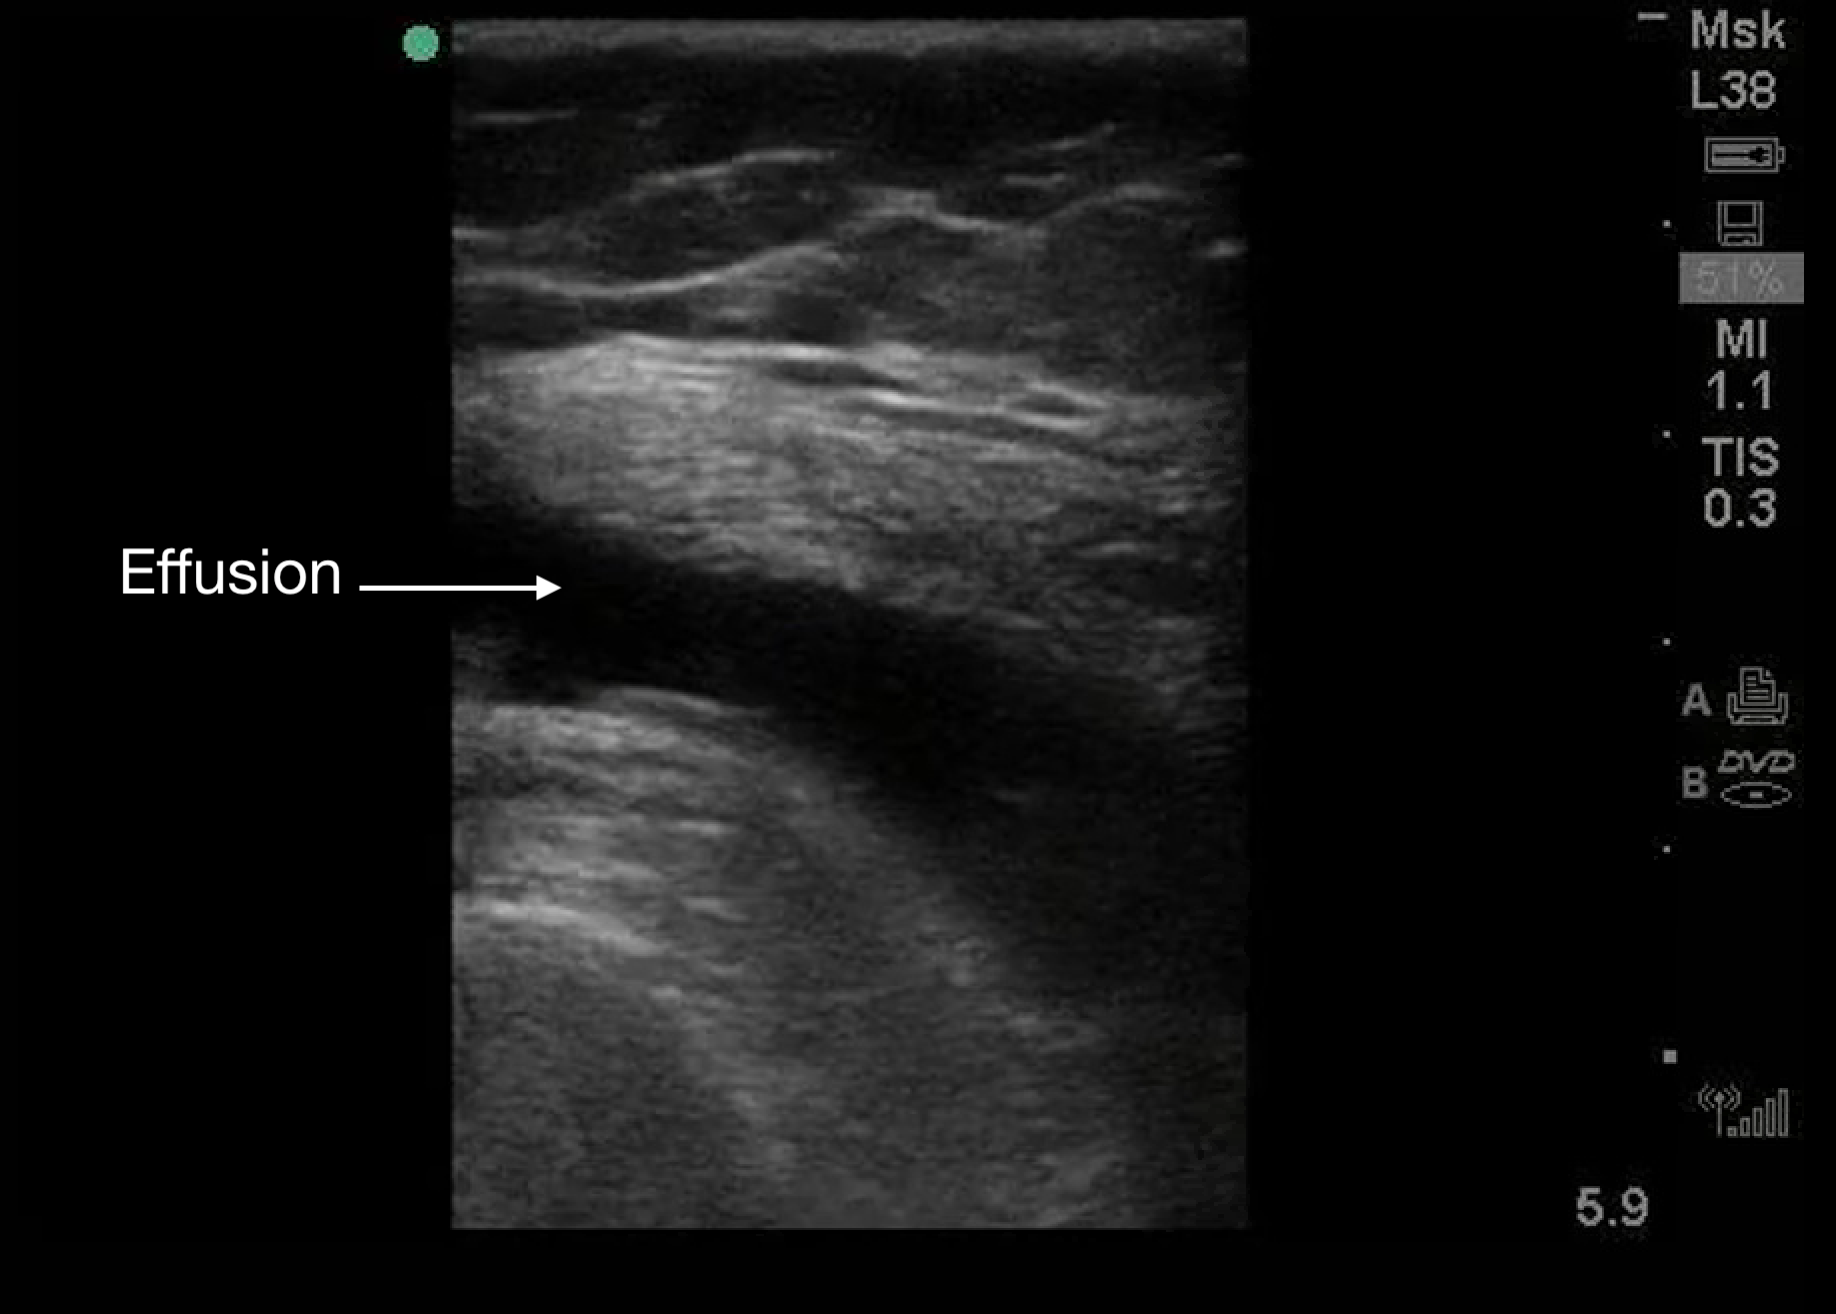

Effusions

Appear as black (anechoic) areas within the joint space on ultrasound.

Figure 8.

A knee effusion seen with a linear transducer. Transducer positioning is the same as Figure 2C.

Presence of irregular internal echoes may indicate complex effusions due to:

- Hematoma.

- Pus.

- Fibrinous material.1

o POCUS is useful for guiding arthrocentesis, allowing precise aspiration of fluid from the joint space.3,5,9